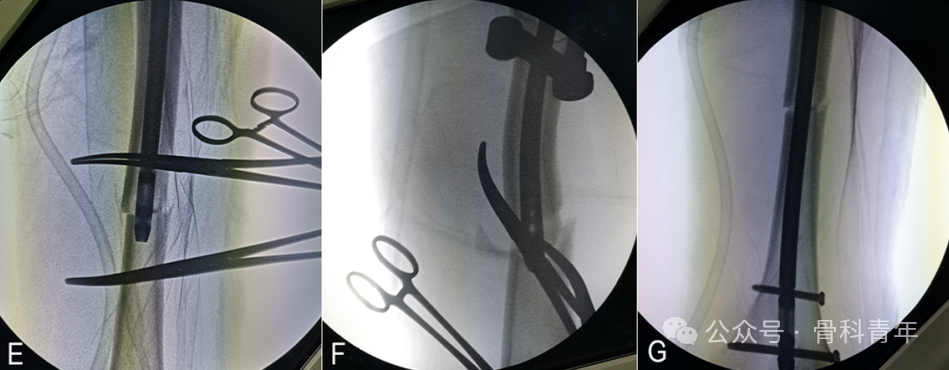

第二步:复位外展畸形。

与屈曲畸形的复位类似,屈曲畸形为冠状位上采用血管钳复位,外展畸形为在矢状面上复位。在骨折线近端1cm,股骨前方轴线内侧1cm处作小切口,依同法置入血管钳,贴于股骨近端外侧皮质置入,复位外展的股骨近端。如单血管钳复位困难,可置入第2把血管钳: